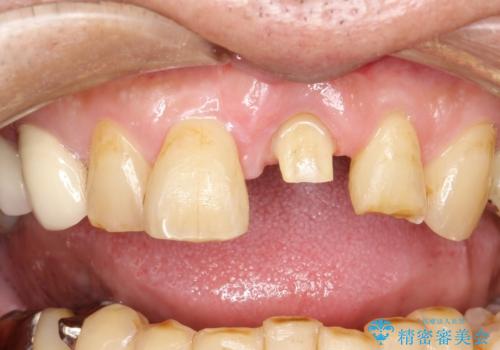

- 左の前歯で硬いものを咬んだら、歯からバキッと音がしてその衝撃で痛みが出た、その後前歯がゆれると来院されました。

左上1が水平的に割れている状態で、歯冠を取り除くと神経が露出しており、唇側はかなり歯肉縁下で破折しており、そのままではかぶせものを入れるのは難しい状態でした。

抜かずになるべくその歯を残して使っていきたいとのことで、

根管治療をした上で歯を引っ張りだして(エクストリュージョン)、その後、骨外科にて歯周組織を整えた上で、かぶせものを入れていく治療計画をたてました。